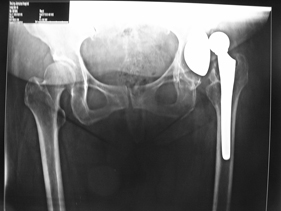

rivision total hip replacement for dislocation and severe bone defect

(post-op)rivision total hip replacement for dislocation and severe bone defect

anterior-posterior view of left hip